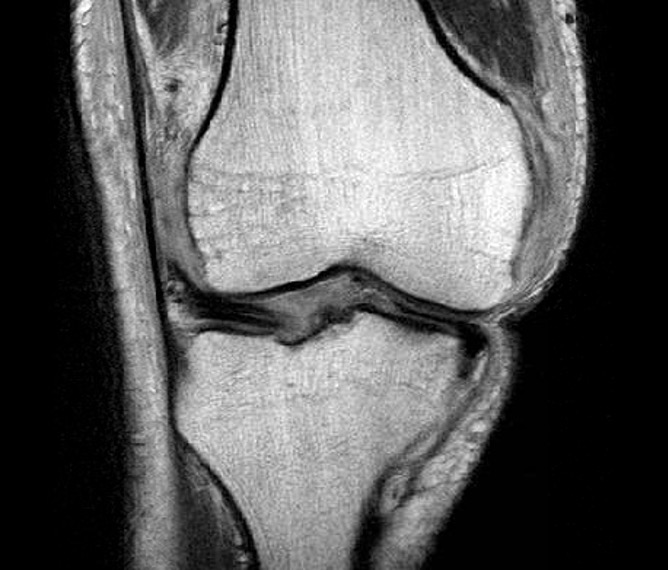

Medial dimpling Entrapped vastus medialis post knee dislocation on Coronal and Sagittal MRI

Coronal MRI of left knee demonstrating proximal MCL tear, with sagittal demonstrating complete disruption of ACL / PCL